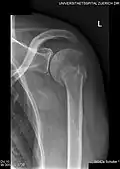

X-ray at left shows anterior dislocation in a young man after trying to get up from his bed. X-ray at right shows same shoulder after reduction and internal rotation, revealing both a bony Bankart lesion and a Hill-Sachs lesion. -